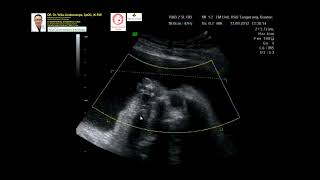

Phocomelia - Amelia Dr Wiku Andonotopo

576

9:02